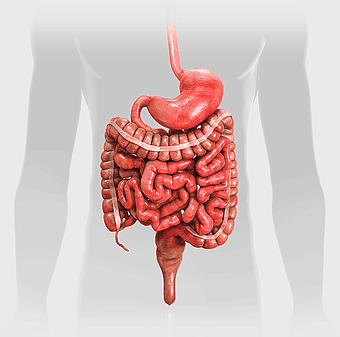

human gastrointestinal tract anatomy, human digestive system illustration, gastrointestinal disease symptoms, human body organ diagram, internal organ visualization, medical anatomy study, digestive health awareness -

Crohn's disease illustration, gastrointestinal tract diagram, large intestine anatomy, digestive system cartoon, medical illustration, human anatomy study, chronic inflammatory bowel condition -

human digestive system, gastrointestinal tract anatomy, liver function, stomach and intestines, digestive health, internal organs diagram, human body systems -

Gastrointestinal tract anatomy, Stomach health, Crohn's disease symptoms, Digestive system, Intestinal inflammation, Human anatomy illustration, Medical diagram -

digestive system diagram, gastrointestinal tract chart, human anatomy illustration, small intestine function, digestive process visualization, internal organ layout, metabolic system overview -

human digestive system illustration, gastrointestinal tract diagram, human body organ system, labeled digestive system, digestive anatomy chart, human internal organs, alimentary canal visualization -

Gastrointestinal tract diagram, Small intestine anatomy, Large intestine function, Apparato digerente illustration, Digestive system structure, Intestinal health, Human anatomy organs -

Gastrointestinal tract illustration, leaky gut syndrome symptoms, small intestine diagram, large intestine function, digestive system health, human anatomy chart, internal organ visualization -